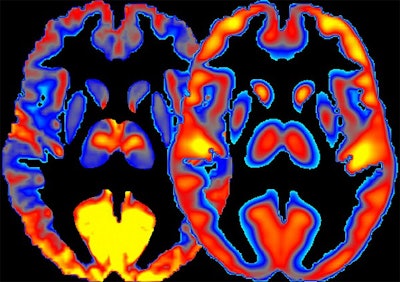

Data from a combination of FDG-PET and functional MRI (fMRI) scans revealed the extent to which alcohol intake can alter patterns of energy use and neuronal activity in the brain, according to an article published online February 11 in Nature Communications.

Combining the FDG-PET and fMRI allowed the group to identify regions of the brain where glucose metabolism exceeded the underlying brain activity. These "high-cost" regions, characterized by low brain activity, were associated with increased alcohol consumption.

"In heavy drinkers, we saw less regional power ... in the thalamus, the sensory gateway, and frontal cortex of the brain, which is important for decision-making," first author Dr. Ehsan Shokri-Kojori said in a statement. "These decreases in power were interpreted to reflect toxic effects of long-term exposure to alcohol on the brain cells."